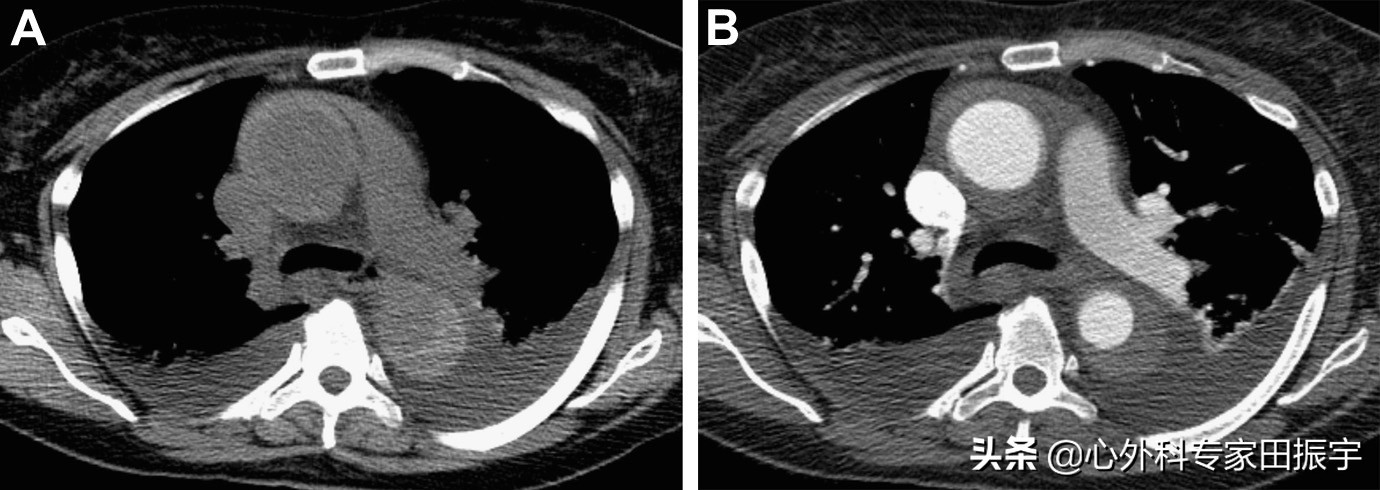

主动脉壁间血肿

图6 在一名59岁突发胸痛和高度怀疑主动脉夹层的59岁妇女身上获得的平扫CT(A)和增强CT图像(B)显示,A型壁间血肿既累及升主动脉,也累及胸降主动脉,并伴有相关的双侧胸腔积液。这些积液的预后意义仍不清楚。

确诊IMH的类型具有预见预后和指导治疗的意义。Stanford A型IMH与B型IMH(图7)相比,A型IMH与心包/胸腔积液、夹层、动脉瘤形成、破裂和死亡的风险增加有关。然而,与Stanford A型主动脉夹层治疗不同(外科手术是标准),在Stanford A型IMH的治疗中仍然存在争议。虽然韩国和日本的研究表明,在A型IMH中,初始药物治疗的结果可以接受,但北美和欧洲的研究更经常推荐手术治疗。